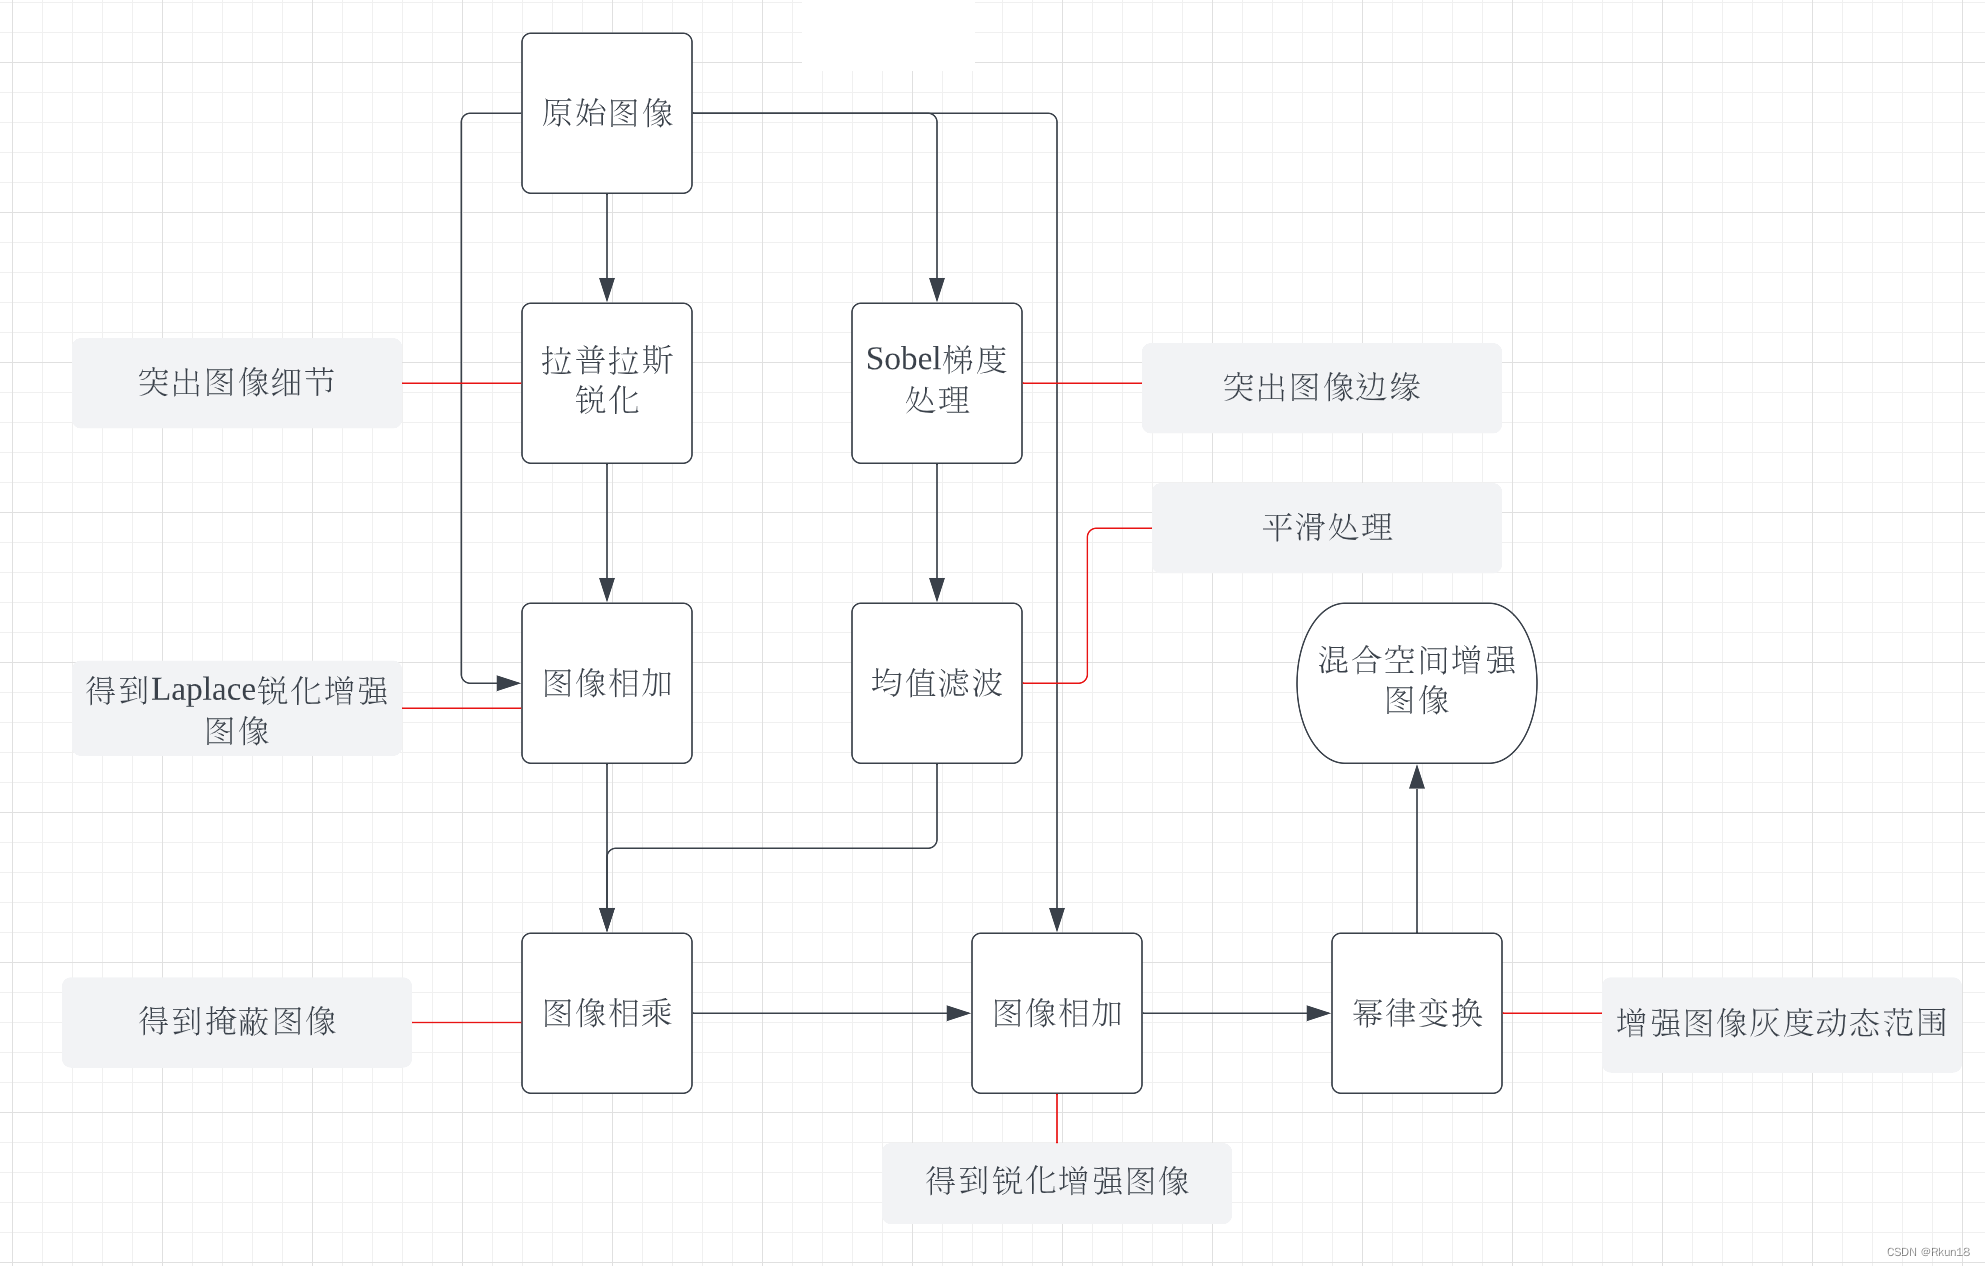

这里使用人体骨骼扫描图像来说明。具体流程如上图,由于人体全身骨骼扫描图像灰度动态范围很窄,并且有很大的噪声内容,使用单一滤波对其增强效果一般。具体作用如图:

从左到右,从上到下依次是:

1:原始图像:

2:1拉普拉斯变化后:

图像全身骨骼扫描,图2为原始图像拉普拉斯变换后的结果,细节信息丰富,同时噪音变多。

3:原始图像与拉普拉斯变换后图像相加得到拉普拉斯锐化增强图像:

4:原始图像Sobel处理 :

图4为原始图像经过Sobel算子处理后结果,边缘信息丰富。

5:均值滤波对4进行平滑:

图4进行空间平滑滤波得到图5,保留图像边缘信息,同时减小了噪声。

6:3*5得到的掩蔽图像:

将图3与图5相加得到图6,发现图6的强边缘优势和可见噪声相对减少。

7:原图与掩蔽图像相加得到的锐化增强图像:

图像的大部分细节更清晰。

8:对7进行灰度幂律变换得到最终结果:

图8进行幂律变换后增大了一些噪声,但同时人体结构更加清晰完整,人体轮廓清晰度也有一定提高。

上图更能直观地观察到图像变换后的差异。

文章介绍了混合图像增强技术在处理人体骨骼扫描图像中的应用,包括使用拉普拉斯变换增强细节,Sobel算子突出边缘,以及灰度幂律变换优化图像对比度。通过一系列图像处理步骤,实现了在保持细节的同时减少噪声并增强图像清晰度。